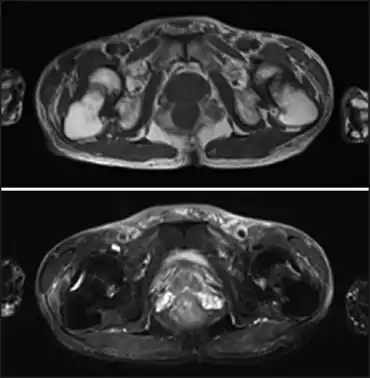

Fanconi syndrome due to adefovir-image demonstrates low-intensity femoral neck fractures and high-intensity bone edema in both femoral necks